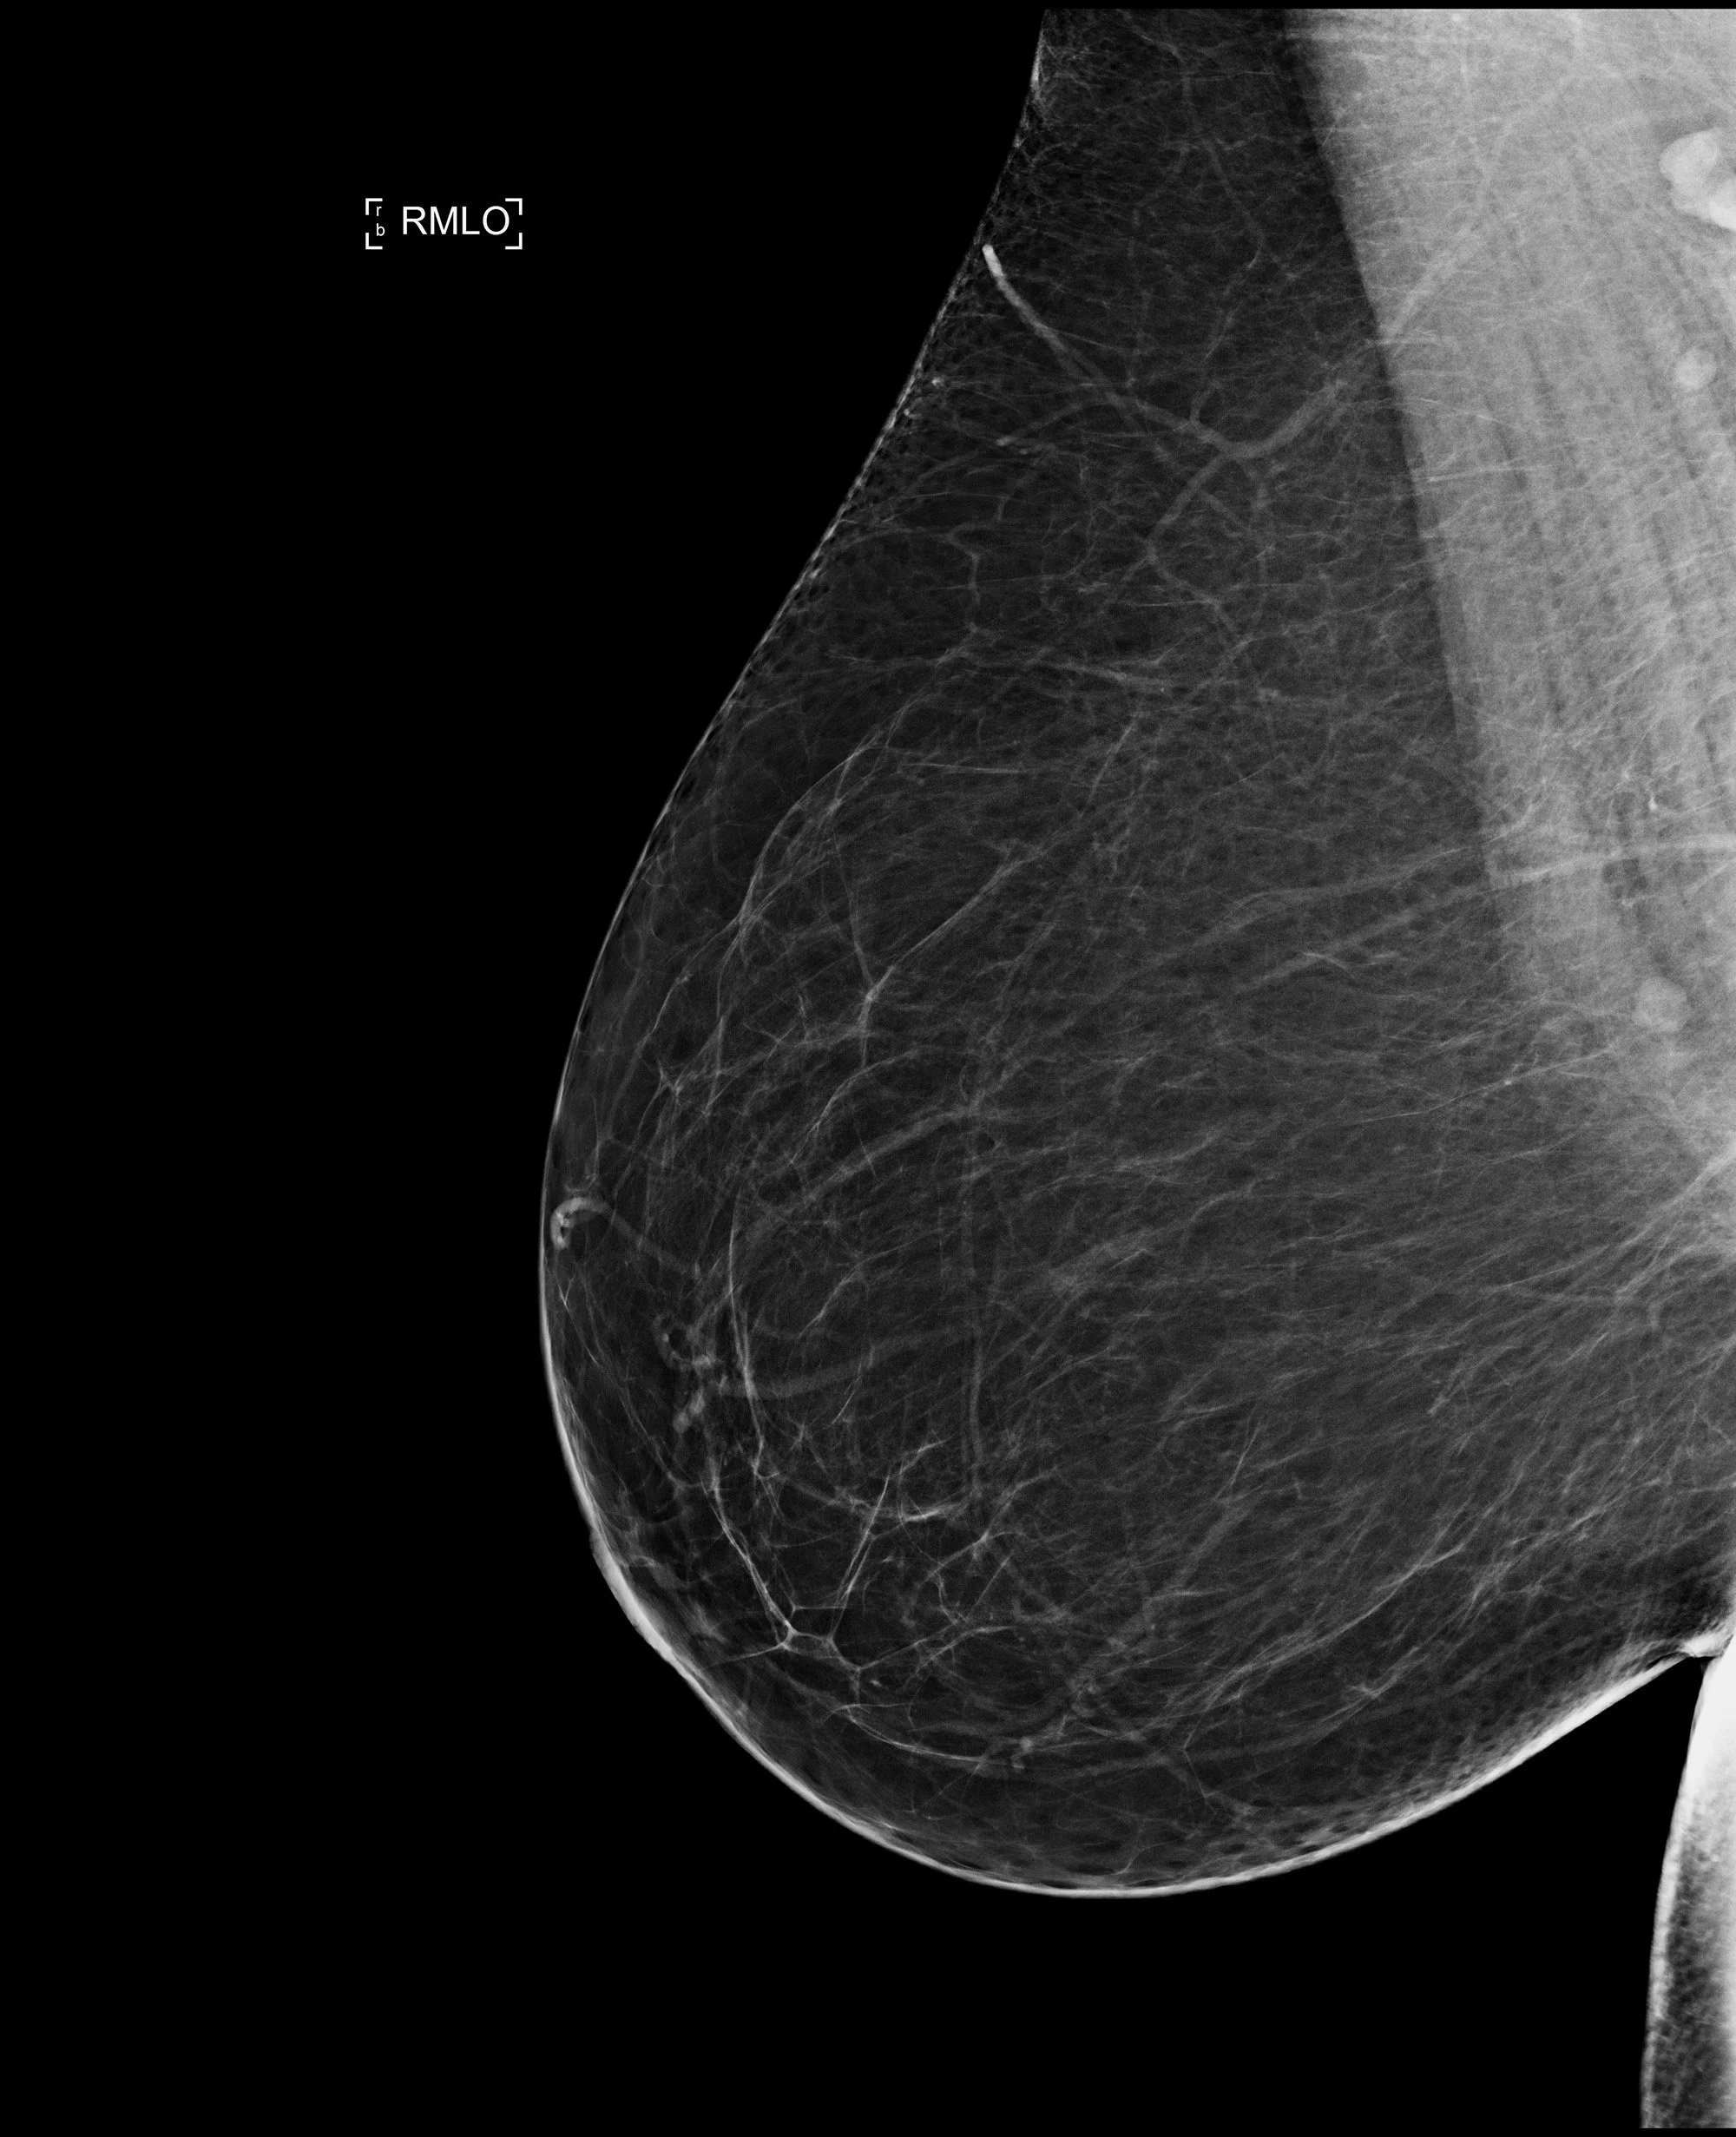

Mammografie

Untersuchungsablauf Mammografie:

Dosierter Druck auf die Brust ermöglicht eine detailgenaue Abbildung des Drüsengewebes. Dadurch gelingt die frühe Darstellung eines (noch nicht tastbaren) Brustkrebs auf dem Röntgenbild. Das Auffinden von bösartigen Mikroverkalkungen ist nur mit der Mammografie möglich. Es werden 2 Aufnahmen pro Seite in dosissparender digitaler Flachdetektortechnik angefertigt. Bei Bedarf werden in unserem Institut Schichtaufnahmen der Brust ergänzt (Tomosynthese). Anschließend tastet der Radiologe die Brust ab. Im Bedarfsfall (dichtes Gewebe, unklarer Befund im Röntgen) erfolgt ein ergänzender Ultraschall (Sonografie). Nach wie vor ist die Mammografie die wichtigste Vorsorgeuntersuchung zur Früherkennung von Brustkrebs.